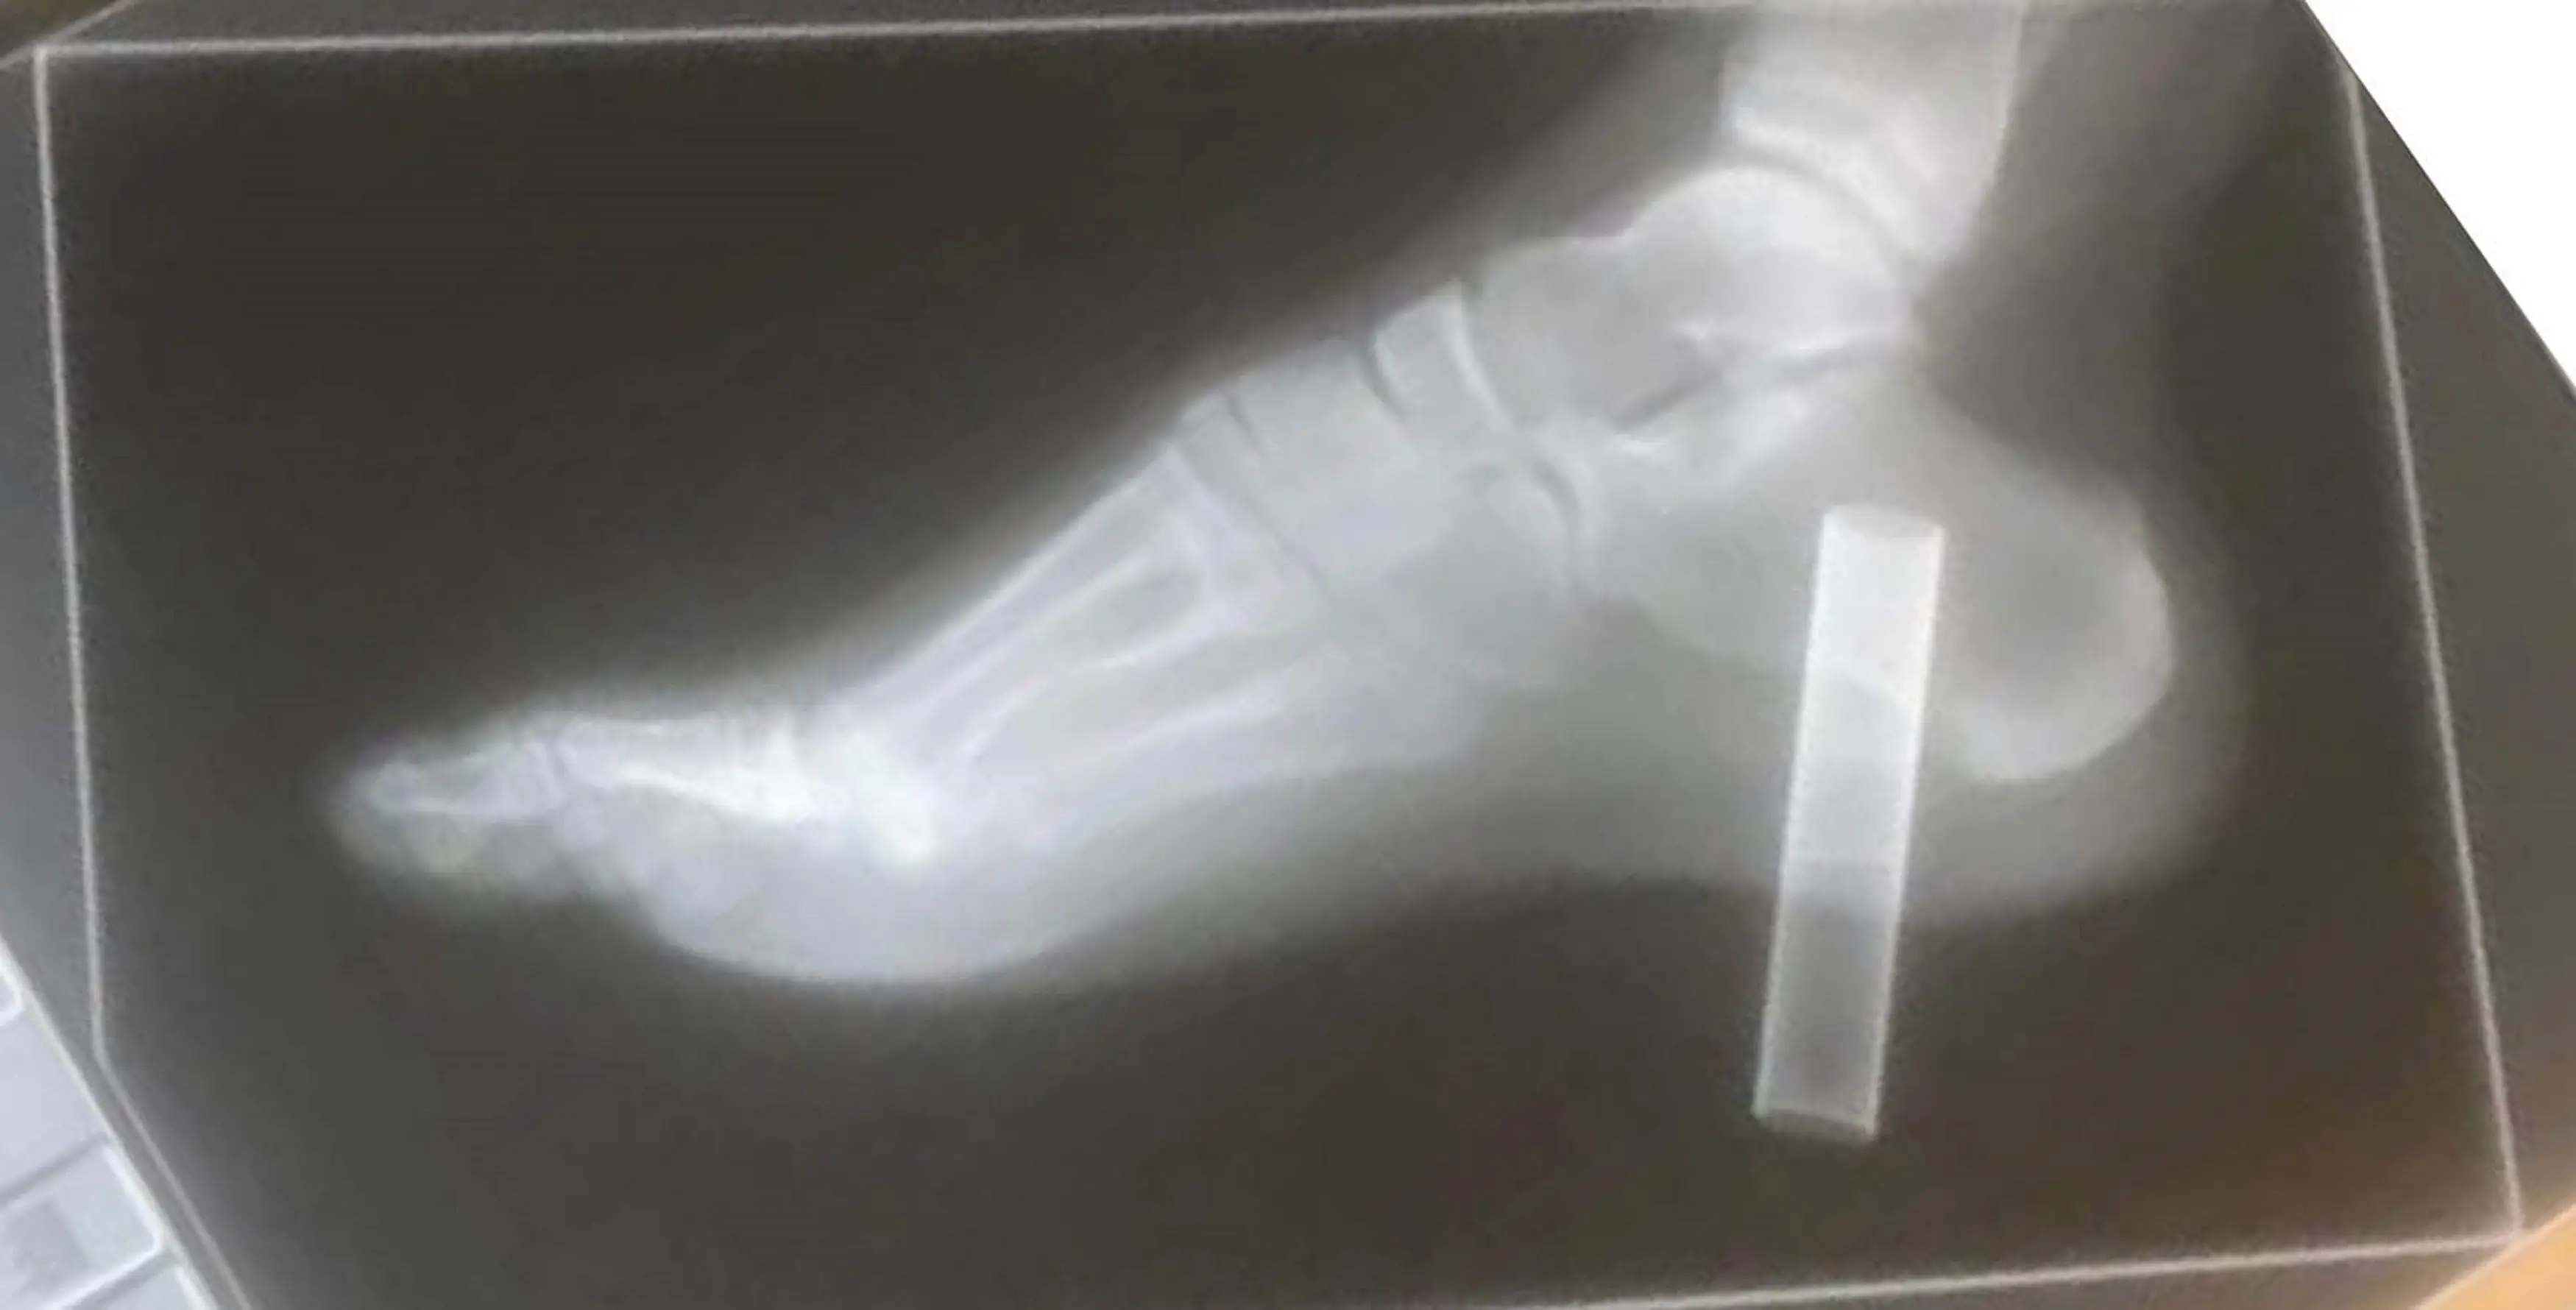

"The size and width of the puff bar went the majority of the way in, and jammed into the top of the heel bone, which cracked it. It was a clean cut of flesh gone. Harley was actually quite calm, probably because the adrenaline kicked in and he wasn't feeling anything."

Pictures of the injury were shared on social media by Harley's grandmother Andrea Keen, with the family warning people to dispose of their vapes properly to avoid another nasty injury like the one he suffered.

The boy's grandma said he'd been wearing '£200 shoes with a really thick sole' which the discarded vape had punched right through.